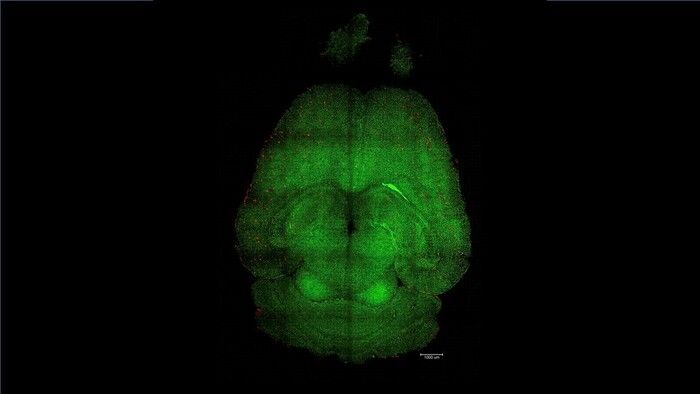

Nanoparticelle che non trasportano molecole terapeutiche ma che sono esse stesse il trattamento hanno fatto regredire la malattia di Alzheimer nei topi : invece di cercare di curare i neuroni, agiscono come interruttori che resettano il sistema vascolare del cervello, permettendogli di riguadagnare la sua capacità di eliminare proteine e altre molecole indesiderate che si accumulano nelle malattie neurodegenerative come Alzheimer e demenza. Il risultato, pubblicato sulla rivista Signal Transduction and Targeted Therapy, si deve al gruppo di ricercatori guidato dall'Istituto di Bioingegneria della Catalogna (Ibec) spagnolo e dal West China Hospital della Sichuan University.

Il cervello umano contiene circa un miliardo di capillari, che svolgono un ruolo cruciale nel mantenimento della sua salute, ed è circondato dalla barriera emato-encefalica, il filtro che impedisce l'ingresso di sostanze pericolose come batteri o tossine.

I ricercatori coordinati dall'italiano Giuseppe Battaglia dell'Ibec hanno usato topi geneticamente modificati per produrre maggiori quantità della proteina beta-amiloide e sviluppare così un declino cognitivo simile a quello dell'Alzheimer, e gli hanno somministrato tre dosi di nanoparticelle . Dopo 6 mesi dal trattamento , un animale di 18 mesi, che equivalgono a circa 90 anni di un essere umano, aveva recuperato del tutto il comportamento di un topo sano.

"L'effetto a lungo termine deriva dal ripristino della vascolarizzazione cerebrale ", afferma Battaglia. "Pensiamo che funzioni con un meccanismo a cascata: quando si accumulano specie tossiche come la beta-amiloide la malattia progredisce. Ma una volta che il sistema vascolare è di nuovo in grado di funzionare - sottolinea il ricercatore - inizia a eliminare la beta-amiloide e altre molecole dannose, consentendo all'intero sistema di ritrovare il suo equilibrio ".